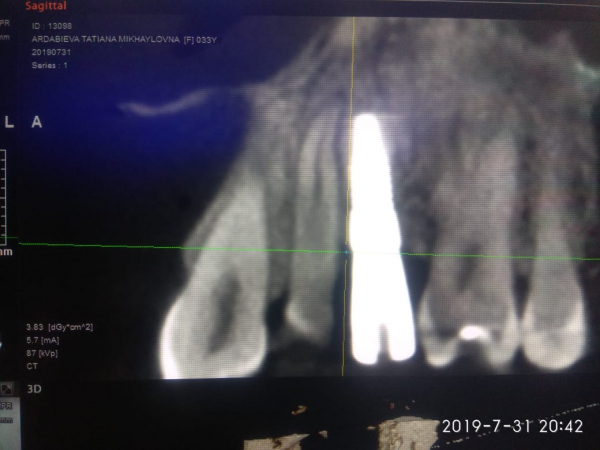

Мне установили 2 недели назад имплант. Зуб расположенный рядом с имплантом полностью здоров, но после установки импланта стал при постукивании болеть. Сделала снимок КТ. Имплант установлен близко к корню. Имплантолог сказал, что они в разных плоскостях стоят и ничего страшного нет, все в порядке. На мой вопрос пройдет ли мой зуб и когда, он ответить не смог.

Да, имплантат расположен близко к корню соседнего зуба, но без оценки полного КЛКТ сложно определить границы. За зубом следует наблюдать. Если чувствительность в течение месяца не снизится, то лучше имплант извлечь.